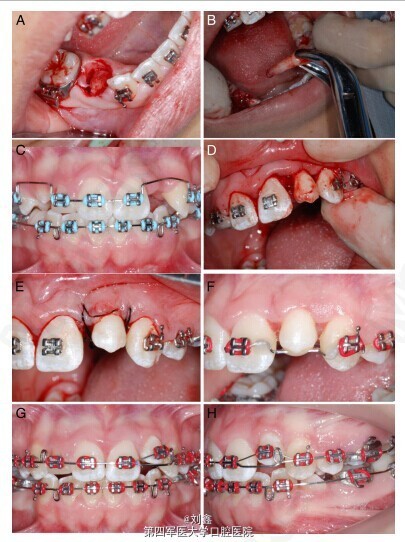

该患者为未成年女性,13 岁,因牙列不齐,影响美观要求正畸治疗。通过对患者的临床检查和曲面断层照片检查,发现患者上颌 15、22、25、35 牙齿尚未发育完全,12 牙齿发育过小;咬合关系和上下颌骨关系正常(图 1)。 根据患者的具体情况,制定详细的治疗计划。首先应用固定矫治器将 14 和 24 移向远中(图 2 A-D),13 随后萌出。21 和 23 之间的空间也被打开。依据 CT 三维影像确定移植位点牙齿的准确数据,考虑到 45 的大小、牙根的发育程度等情况,选择将 45 拔出后移植至 22 的位置。手术预备移植位点的牙槽窝 (图 2E,F)。 拔出 45,移植入预备好的 22 牙槽窝(图 3A-F)。缝合伤口,术后用树脂将 45 与邻牙固定两个月,四个月后开始移动 45(图 3G,H)。 该病例整个治疗过程持续 32 个月,治疗结束时临床和影像学检查显示,移植的前磨牙外形美观,牙根发育已完成,根管也已完全闭锁,预后良好(图 4A-E)。